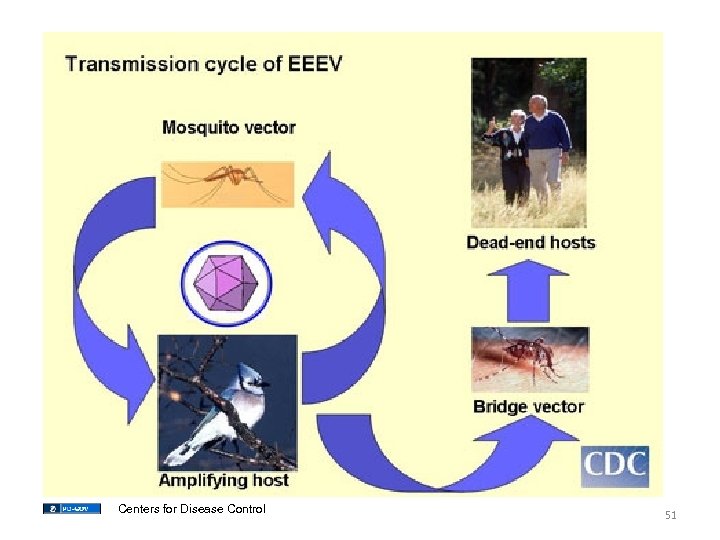

Centers for Disease Control 51